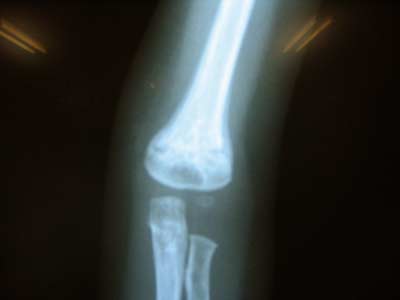

【整形の先生のお話】

・すっかりよくなっている。

特に何もしなくても自然と使えるようになる。

こないだの写真と比べて、新しくできた骨が白くしっかりしてきた。

また同じように打ったりしなければ折れる心配はない。

しばらく一週間おきにレントゲンをとって、

しっかりしてきたら2週間おきにする。

骨のでき次第で個人差はあるが、

だいたい3ヶ月で治るということ。

前回うっすらと白かった部分がはっきりし、

骨もだいぶ太くなりました。